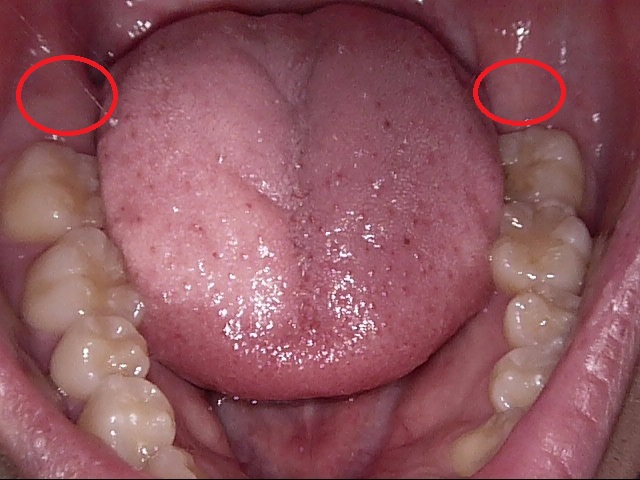

お口を見てみると、親知らずは生えていません。赤丸部分に歯ぐきの下に埋まっているようです。